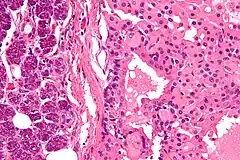

![]() Oncocitoma que afecta a la glándula parótida. | ||

Fue descrito originalmente por Zippel en el año 1942. En 1974 Klein y Valensi publicaron sus hallazgos sobre una serie de 13 casos de oncocitomas renales. Desde entonces las características de la célula oncocítica que forma este tipo de tumores ha sido definida con precisión: amplio citoplasma muy eosinófilo, abundante número de mitocondrias, núcleo central y ausencia de atipias.[2][3][4][5]